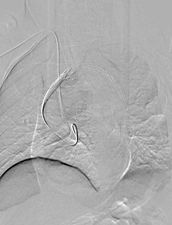

经过周密计划,该科室制定了分阶段杂交手术方案:心血管外科先通过2处5cm的手术切口行颈动脉—锁骨下动脉搭桥,建立血流通路;接着介入科团队接力,通过3处不超过1cm的微创伤口完成胸主动脉夹层腔内覆膜支架隔绝术,并用血管塞精准封堵左锁骨下动脉起始段以避免术后支架内漏。

△手术按术前计划有条不紊地进行中。

△注:支架精准定位,稳定释放,成功以“人工血管”将主动脉破口隔绝。